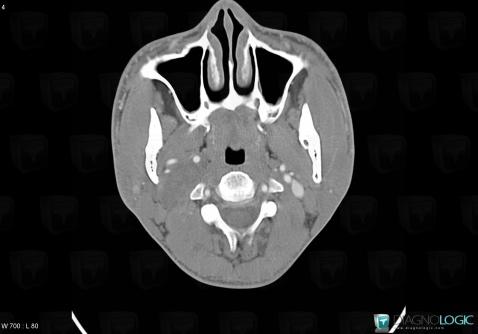

Schwannome, Espaces profonds-cou, Scanner

Voici les informations spécifiques à l'image clé ci dessus:

- Diagnostic Schwannome, Localisation(s) Espaces profonds du cou, comportant les gammes Masse solide cervicale, Lésion de l'espace carotidien